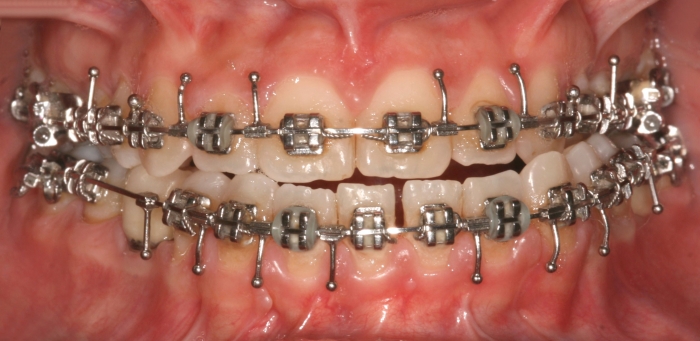

Mordida inicial

Mordida final